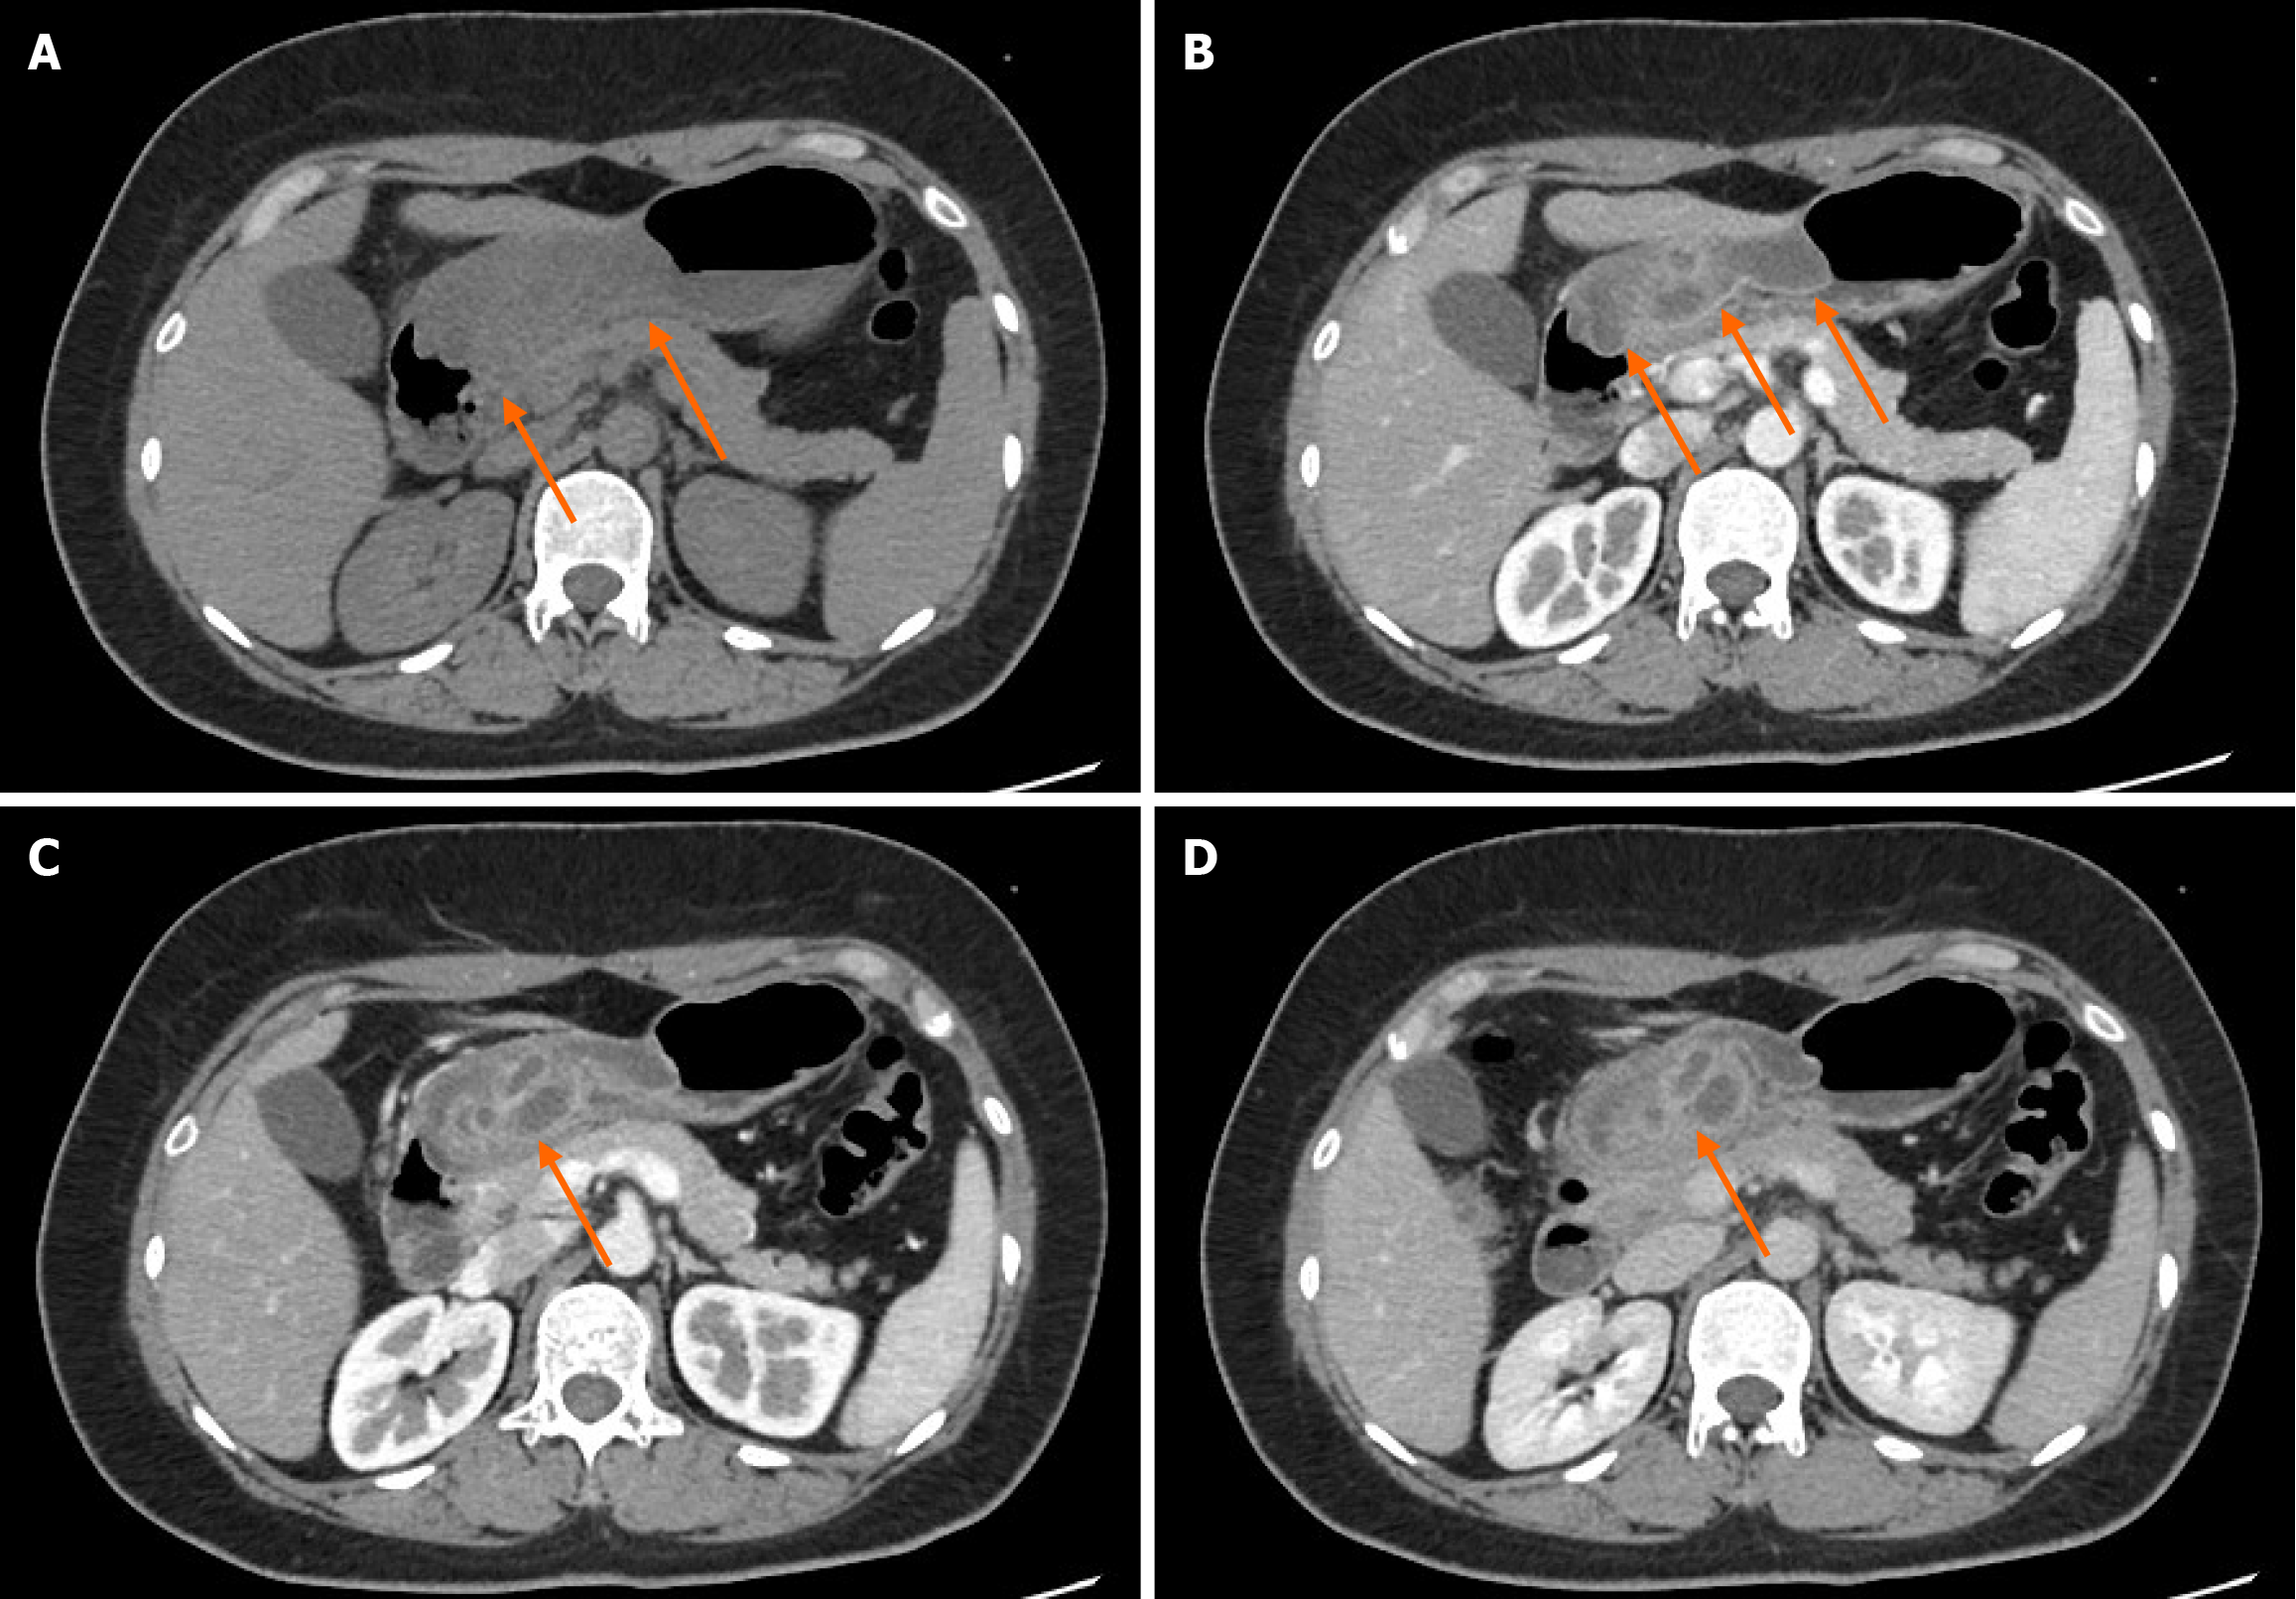

Figure 1 Gastroscopy showing a submucosal bulge in the gastric antrum.

A: White-light gastroscopy revealed congestion and edema of the gastric antral mucosa, with a 4-cm submucosal bulge on the anterior wall; B: Close-up view of the lesion; C: Optical electronic chromoendoscopy demonstrated the micro-surface and microvascular structures of the lesion; D: Application of pressure with a pair of biopsy forceps confirmed a soft texture.